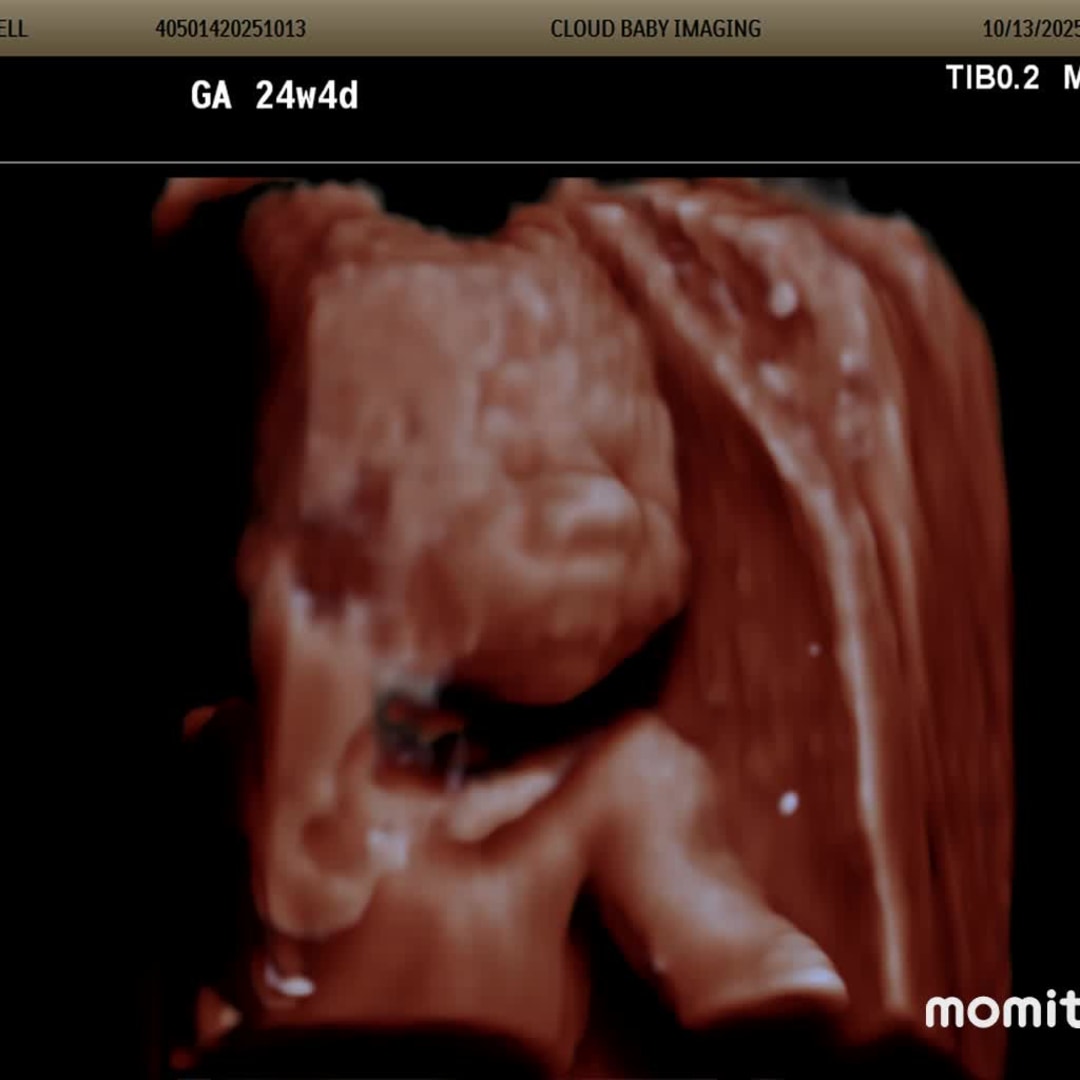

Wren’s Selfies